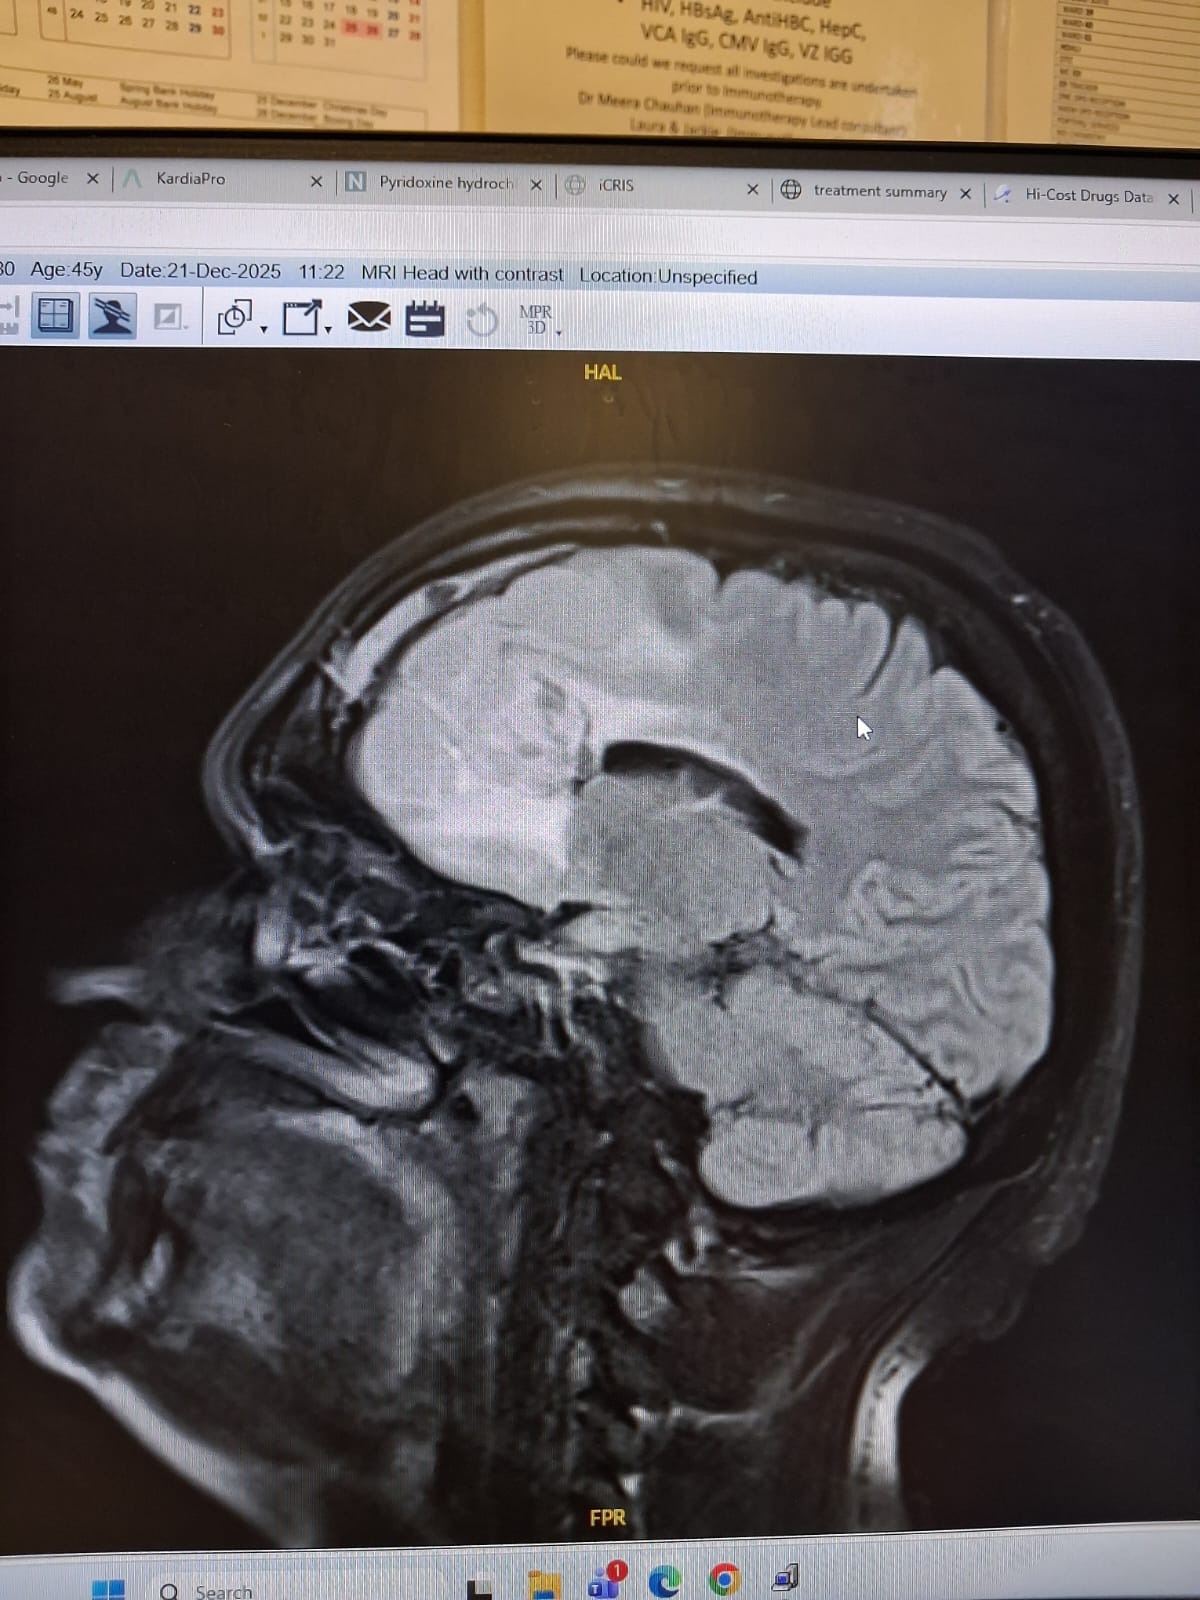

To give you a small back story 17 years ago after having a seizure the doctors found a grade 3 right frontal lobe anaplastic astrocytoma. He was given major brain surgery followed by intensive radiotherapy. After the fight of his life he was given a survival rate of 5 years. He surpassed that by an extra 12 year. He was incredibly lucky.

Then in December 2025 he started getting headaches again, after a scan it revealed the cancer was back and worse than ever, it is bigger and has progressed into grade 4. Alot of treatments are not available for him, it is inoperable, radiotherapy can not be done again. Leaving us with only the option of chemotherapy, even with this they can only give us around a year. We are devastated.